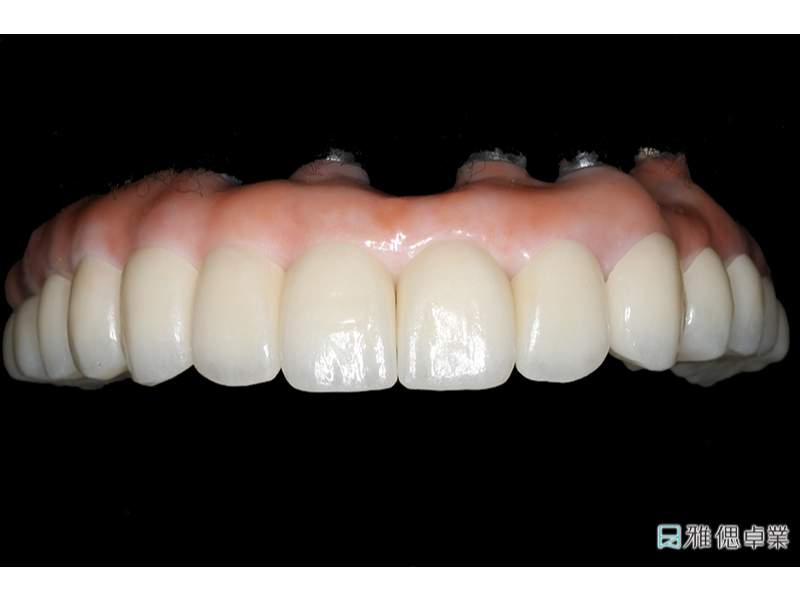

臨時假牙模型下顎

假牙模型下顎

All on 6正式假牙(下顎)